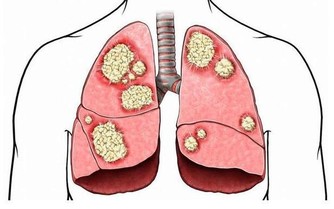

10. 降膽固醇藥Statins減少壞膽固醇。

許多人為避免血管堵塞或減少心血管疾病,而攝取降膽固醇藥物,雖然研究證明這種藥物有效,卻這些研究卻只局限於過去有心臟病史的病人身上,因此真正的功效還有待商榷。